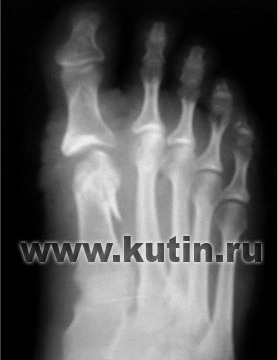

Пациентка Т., 33 лет.

HV

обеих стоп, более выраженное

отклонение I пальца на правой

стопе. Комбинированное

плоскостопие. |

|

2007г. |

А |

Б |

Первым этапом

выполнена коррекция деформации

(А) переднего отдела правой

стопы с устранением

вальгусного отклонения I пальца.

На контрольной (Б)

рентгенограмме (второй день

после операции) видна проекция

дистальной остеотомии

I плюсневой

кости. |

Рентгенограммы правой стопы до

(А) и после операции (Б) |